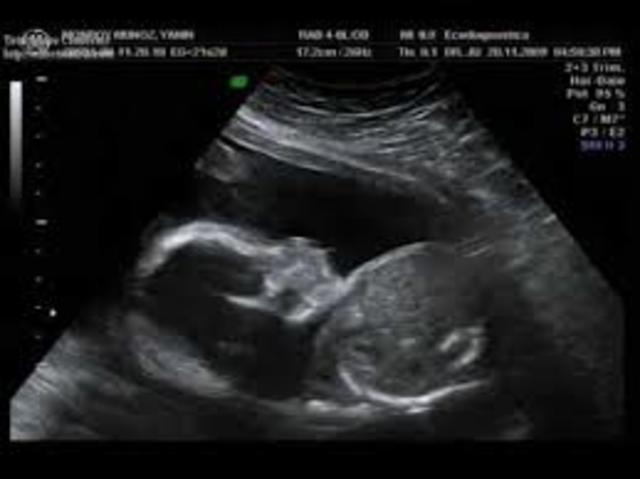

La cara va adquiriendo una forma más normal y redondeada, los ojos que están muy separados se juntan un poco, y también suben un poco las orejas llegando casi hasta su situación definitiva, ya que cuando se forman están muy baja, ya existe un primordio del intestino, se llaman asas intestinales, Al final de esta semana las medidas del feto son: 8,5 cm de longitud y su peso oscila entre 15 y 20 gramos.

Los ojos y las orejas del bebé han alcanzado su posición definitiva. El bebé ya puede bostezar, hacer gestos faciales o tener hipo, dado que su sistema digestivo ya funciona y empieza a poder tragar. Sus cuerdas vocales ya están desarrolladas y podría incluso llorar, Gracias a que los huesos de su oído interno y la mayoría de terminaciones nerviosas del cerebro están ya desarrolladas, el bebé es capaz de distinguir sonidos como su propio corazón o la voz de su madre.

El corazón del bebé sigue su desarrollo y se forman las cuatro cámaras, mientras que el esqueleto también sigue su curso y empieza a formarse el tejido óseo a partir del cartílago suave.